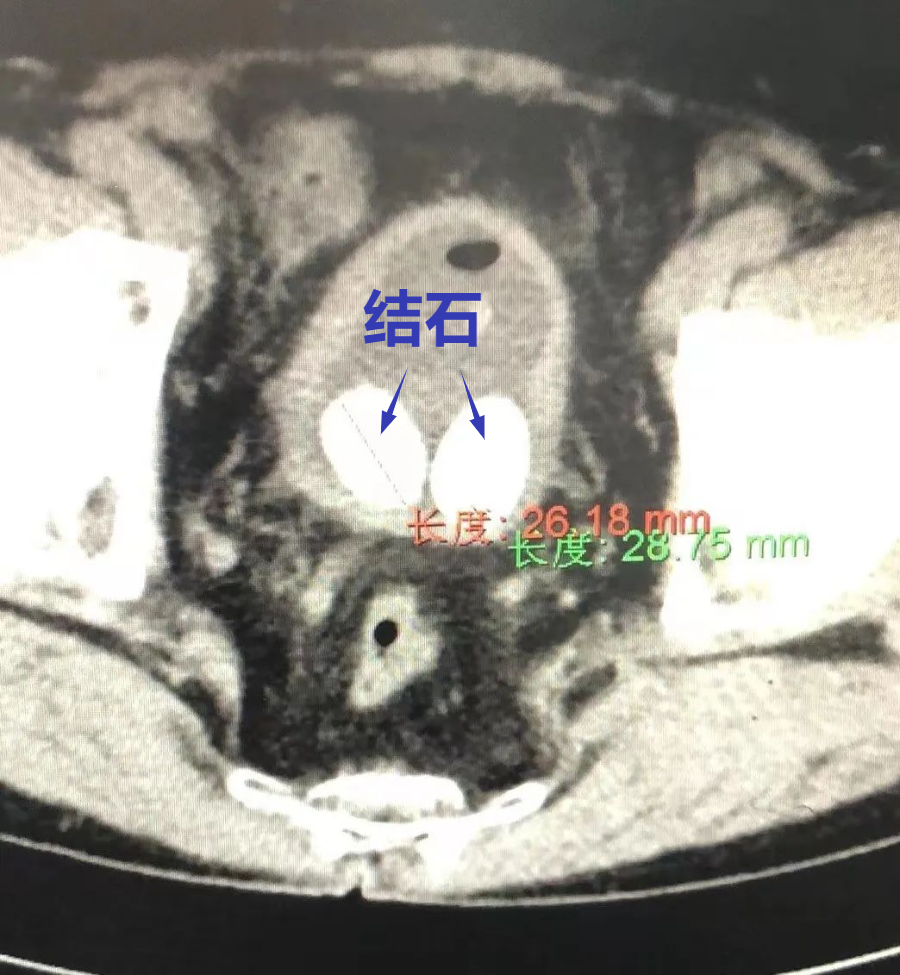

病例来由:1个多月前,外县一位老人因间歇性排尿困难就诊于当地医院,检查发现为膀胱多发结石,最大约3*3厘米,并伴有前列腺增生。前列腺增生是膀胱结石的主要病因,因此处理结石必须同时行前列腺电切术,而前列腺电切术又对患者的身体状况要求高,面对这样一位结石较多较大,需同步开展前列腺电切术的高龄患者,当地医院建议转省级医院进行治疗。

入院完成术前检查后,院泌尿外科与麻醉科认真进行了病例讨论,综合评估老人病情,考虑老人身体条件差、手术的耐受性低、结石负荷大,手术风险极高,常规手术可能需要多次才能解决问题。最终决定先为老人膀胱造瘘,行气压弹道碎石,然后结合钬激光碎石,将结石以相对较短时间粉碎、清除,最后行前列腺电切术。力求在尽可能短的时间内将膀胱结石清除干净,恢复尿路系统畅通,保护膀胱功能,改善生活质量的治疗方案。

征求家属意见后,于10月10日顺利完成手术。术后,患者复查尿路平片,结石清除彻底,治疗效果明显。